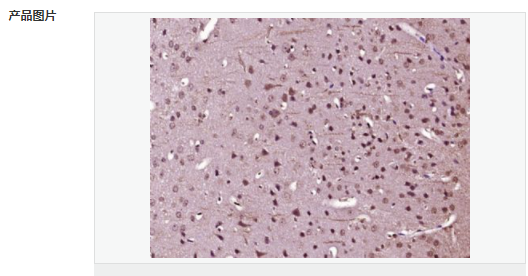

| 產品應用 | ELISA=1:5000-10000 IHC-P=1:100-500 (石蠟切片需做抗原修復) not yet tested in other applications. optimal dilutions/concentrations should be determined by the end user. |